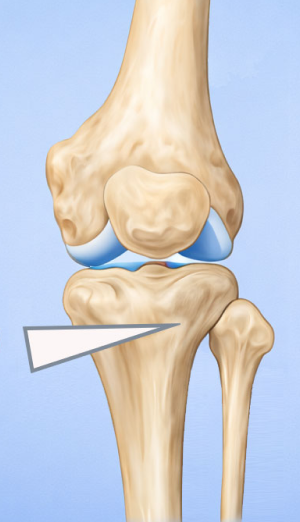

High Tibial Osteotomy (HTO)무릎 아래 뼈인 경골(정강이뼈)의 윗부분(근위부)을 절골하여 다리 정렬을 바로잡는 무릎 교정 수술입니다.

무릎 안쪽 관절이 닳아 O자 다리 형태로 휘어 통증이 생기는 경우, 다리의 축을 바로잡아 무릎 안쪽의 하중을 줄여주는 교정 수술입니다.

관절면과 평행하게 절골하여 각도를 교정

정강이 위쪽 뼈(경골 근위부)를 절골합니다.

약간 벌리거나 닫아서 다리축을 “일자에 가깝게” 교정해서 닳은 안쪽 무릎의 부담을 줄이고 통증 감소 및 기능 향상을 유도합니다.

절골한 부위는 금속판(plate)으로 고정합니다.